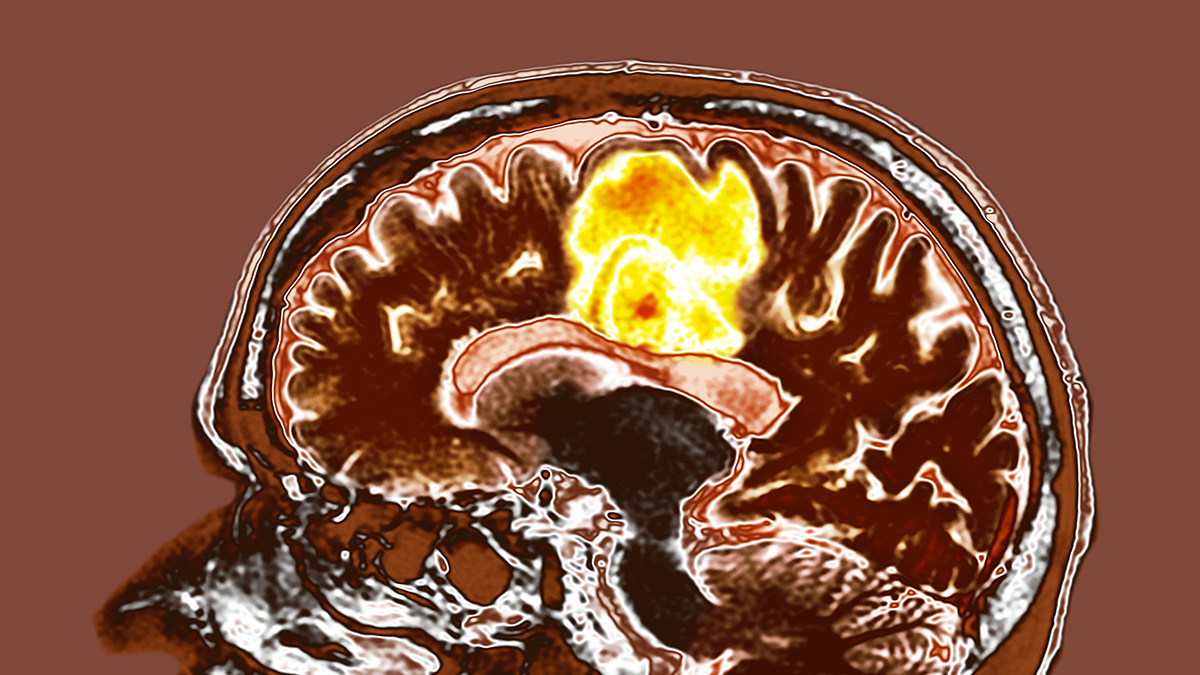

الورم الأرومي

توصلت دراسة جديدة إلى أن اثنين من المكملات الغذائية الشائعة قد يقدمان طريقة جديدة محتملة لعلاج الورم الأرومي الدبقي.

مكملات غذائية لعلاج أورام الورم الأرومي الدبقي